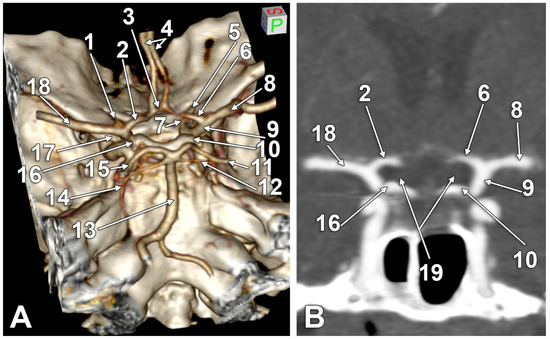

| Gender | Right Side | Left Side | Other Variations | Figure |

|---|---|---|---|---|

| M | type 3 IO A1 SCar | type 3 IO A1 SCar | high BA bifurcation | Figure 3A |

| M | type 3 IO A1 | type 3 IO A1 | Figure 2D | |

| M | type 2 IO A1 | type 1 IO A1 SCar | fenestrated AComA, hypoplastic left A1 | Figure 2A |

| M | type 2 IO A1 | type 2 IO A1 SCar | Figure 4C | |

| M | type 2 IO A1 | type 2 IO A1 | Figure 4A | |

| M | type 2 IO A1 | type 2 IO A1 | – | |

| M | type 2 IO A1 | type 2 IO A1 | Figure 5B | |

| F | type 2 IO A1 | type 2 IO A1 | rotated BA, left PCA displaced towards the ipsilateral A1 ACA | Figure 4D |

| F | type 2 IO A1 | type 2 IO A1 | duplicated AComA | Figure 4B |

| F | type 2 IO A1 SCar SClin | type 1 IO A1 | supraclinoid right A1 | Figure 2C |

| F | type 2 IO A1 | type 2 IO A1 | Figure 3D | |

| F | type 2 IO A1 | type 2 IO A1 | Figure 3B,C | |

| F | type 2 IO A1 | type 2 IO A1 | hypoplastic right A1 | |

| F | type 2 IO A1 SCar | type 2 IO A1 SCar | rotated AComA, hypoplastic right A1 | Figure 5A |

| F | type 2 IO A1 | type 2 IO A1 | rotated BA, left PCA displaced towards the ipsilateral A1 ACA | Figure 5C |

| F | type 1 IO A1 | type 2 IO A1 | left bihemispheric ACA | Figure 2B |